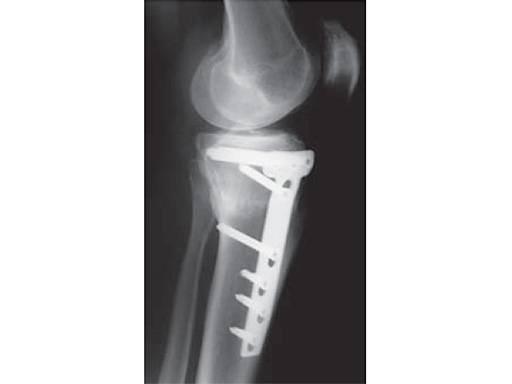

A 68-year-old female.

Case provided by Alex Staubli, Luzern, CH

The correction is planned on a long-leg standing x-ray. After surgery, the mechanical axis should pass through a point 63% on the lateral side of the total width of the tibial plateau in the frontal plane. A transverse or slightly oblique incision is used to avoid damage to the saphenous nerve. The distal fibers of the medial collateral ligament are detached from the tibia. Under fluoroscopic control, two wires are placed in the proximal tibia marking the transverse osteotomy plane. The cut usually starts at the upper margin of the pes anserinus and ends at the tip of the fibula on the lateral side. The wires are placed exactly parallel to the tibial plateau thus taking into consideration the individual tibial slope of the patient. An incomplete cut of the posterior two-thirds of the proximal tibia is performed with an oscillating saw guided by the wires. Continuous irrigation avoids burn injury to the bone. A second osteotomy is now performed in the anterior third of the tibia in an angle of 100 ending above the patellar tendon insertion. A smaller saw blade is used and the complete anterior cortex is cut exactly in the frontal plane. The osteotomy is now gradually opened by inserting flat chisels or a spreader-chisel into the posterior osteotomy cleft. This process may take some minutes and can usually be completed without fracture of the lateral cortex. A bone spreader is now placed in the posteromedial edge of the tibia and the chisels are removed. The leg is extended and the correction is checked with the fluoroscope. A long metal rod is placed between center of the hip joint and center of the ankle joint. The projection of this rod should be at the planned point of correction on the tibial plateau lateral of the midline. Eccentric collapse of the medial joint space may cause accidental overcorrection. In this case pressure on the foot may simulate loading and body weight. The correction can be fine-tuned by opening or closing the spreader. The TomoFix Medial Tibia Plate is now placed in a subcutaneous pocket. The implant is precontoured and usually fits well to the bone surface. The distance holders avoid compression of the medial collateral ligament and the pes anserinus. Three proximal bolts are placed near the subchondral sclerosis zone. The position of the bolts is adapted to the anatomy of the proximal tibia giving optimum purchase for the bolts. An oblique lag screw is inserted distal to the osteotomy. This screw in the first combination hole allows careful compression of the lateral osteotomy hinge and pretensioning of the implant. A stab incision is created on the shaft and the implant is fixed monocortically with bolts. The lag screw and the distance holders are replaced by bolts. The medial collateral ligament is released longitudinally to reduce medial compartment pressure and the wound is closed in layers. An overflow drain may be used. Clinical and experimental work has proven that when this technique is closely followed, corrections up to and over 15 mm can be performed without bone grafting or use of bone substitutes.

The patient is mobilized on crutches on day one after surgery. Partial weight bearing is allowed from the beginning. Biomechanical and RSA studies have proven that postoperative loading of the implant by body weight in standard partial weight bearing and early full weightbearing conditions did not cause loss of correction. Our group now allows the patients to walk without crutches as soon as the postoperative pain allows after this type of surgery. Members of the Knee Expert Group (KNEG) have presently implanted over 1,500 TomoFix medial tibia. The results are extremely positive in respect to osteotomy healing, implant failure, and surgical complications.